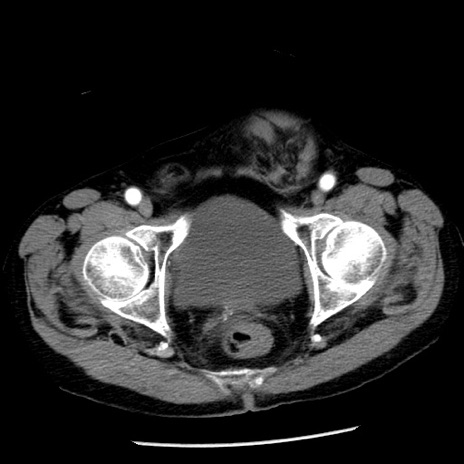

症例26(横断像)

【症例】80歳代男性

【主訴】嘔吐

【現病歴】昨晩2回嘔吐あり、今朝になっても嘔吐あり。来院。

【既往歴】胃潰瘍

【身体所見】意識清明、BT 37.6℃、BP 166/95mmHg、HR 100bpm、SpO2 97%、腹部:平坦・軟、腸蠕動音聴取良好、圧痛なし。

【データ】WBC 21900、CRP 1.46